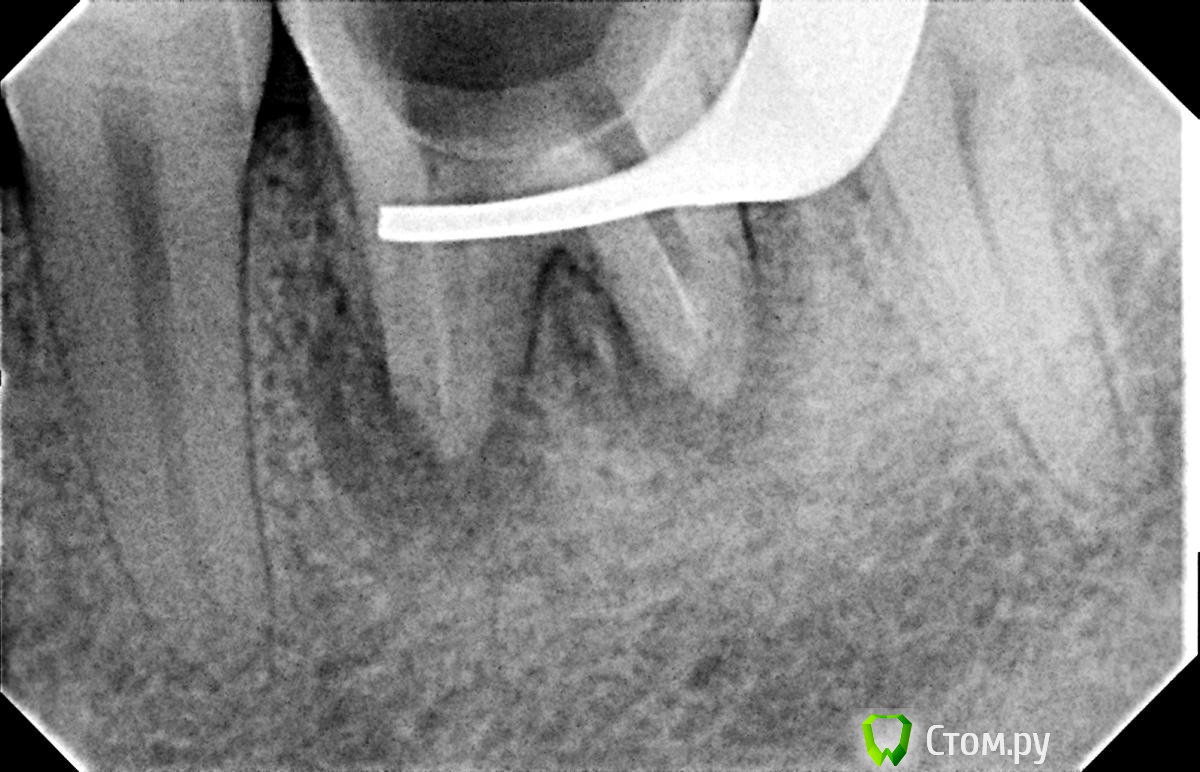

Hans85 Опубликовано 8 января, 2014 Поделиться Опубликовано 8 января, 2014 Только зарегистрировался на форуме,хотелось бы познакомится с коллегами.для начала выкладываю небольшой кейс с названием "Почти мини".Направлен пациент прошло 6 месяцев после фиксации композитной вкладки,заболел.Эндо без рук (только контроль проходимости 10 К-file)Rece+ProFile,пломбирование волна.Всем здравствуйте.P.S Сан Саныч привет)). 12 Ссылка на комментарий

Hans85 Опубликовано 8 января, 2014 Автор Поделиться Опубликовано 8 января, 2014 видимо еще не разобрался картинку 1 и 4 местами поменять надо бы,ну и 2 и 3 тоже Ссылка на комментарий

Мартовский Опубликовано 8 января, 2014 Поделиться Опубликовано 8 января, 2014 Только зарегистрировался на форуме,хотелось бы познакомится с коллегами.для начала выкладываю небольшой кейс с названием "Почти мини". Направлен пациент прошло 6 месяцев после фиксации композитной вкладки,заболел. Эндо без рук (только контроль проходимости 10 К-file)Rece+ProFile,пломбирование волна. Всем здравствуйте. P.S Сан Саныч привет)).Отличный доступ и эндо, но желательно выставлять снимок до, с инструментами, и после. Как сказали выше, выстраивать логическую цепочку. Ссылка на комментарий